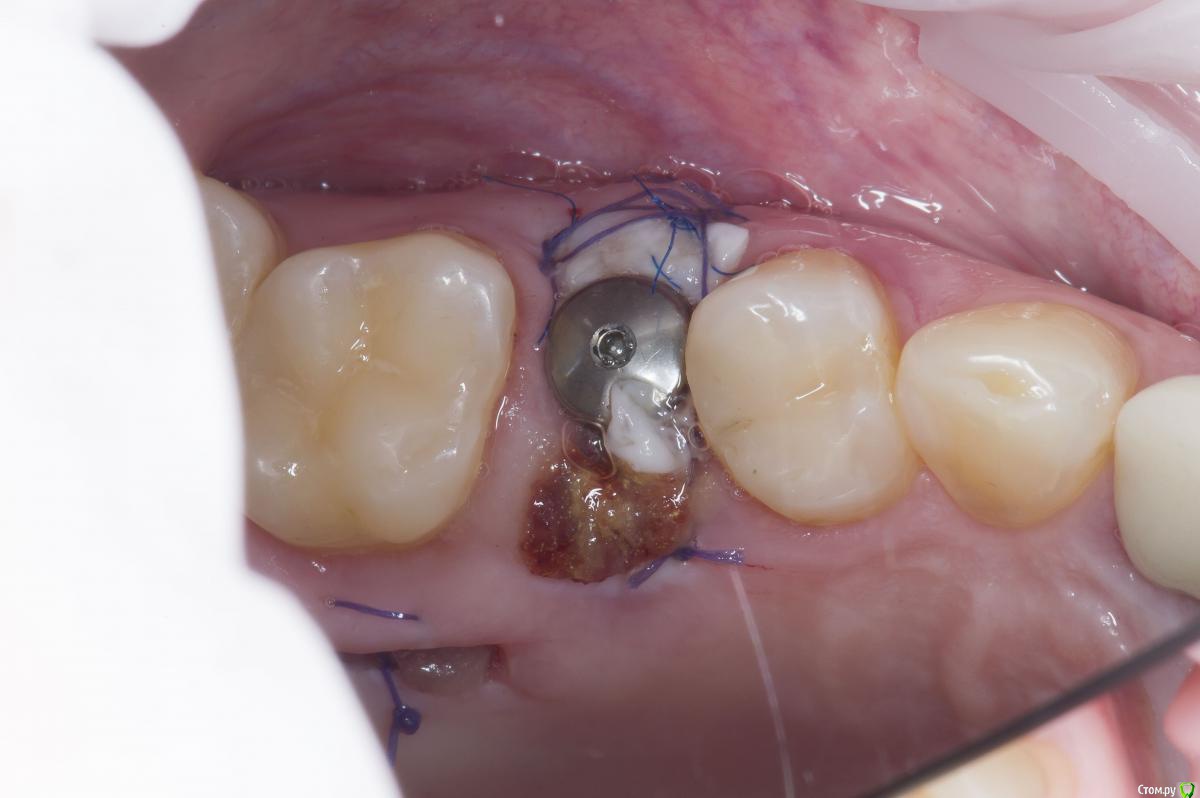

Sampson Опубликовано 10 августа, 2018 Поделиться Опубликовано 10 августа, 2018 (изменено) Очень мило для первого раза.. Здравствуйте коллеги.Сегодня поставил первый свой одномоментныйИзначальная картинаУдалениеСверление и контрольГрафтБолтКТФдмP.S. еще сдт взял с неба и вестибулярно подшил. А с неба заложил prf. Изменено 10 августа, 2018 пользователем Sampson 7 Ссылка на комментарий

Aquarius Опубликовано 10 августа, 2018 Поделиться Опубликовано 10 августа, 2018 Хорошая работа. Только куда графт делся после 3D заполнения? Отсосом забрали? витки импланта видны в лунке, а на предыдущем фото графт есть 1 Ссылка на комментарий

Sampson Опубликовано 10 августа, 2018 Автор Поделиться Опубликовано 10 августа, 2018 (изменено) Хорошая работа. Только куда графт делся после 3D заполнения? Отсосом забрали? витки импланта видны в лунке, а на предыдущем фото графт естья думал с неба он не обязателен:-) Просто ставиш имплан на уровне кости и все;-) Но спасибо учту. Изменено 10 августа, 2018 пользователем Sampson Ссылка на комментарий

Карен Аванесов Опубликовано 10 августа, 2018 Поделиться Опубликовано 10 августа, 2018 Молодец! Не загордись теперь)))) так теперь критика: болт.... забить болт.... ну вы поняли)) 1 Ссылка на комментарий

Evikrol Опубликовано 11 августа, 2018 Поделиться Опубликовано 11 августа, 2018 Отлично, только шахта выходит на вестибулярный бугор, не отдавай ортопеду который любит винтовую. Ссылка на комментарий